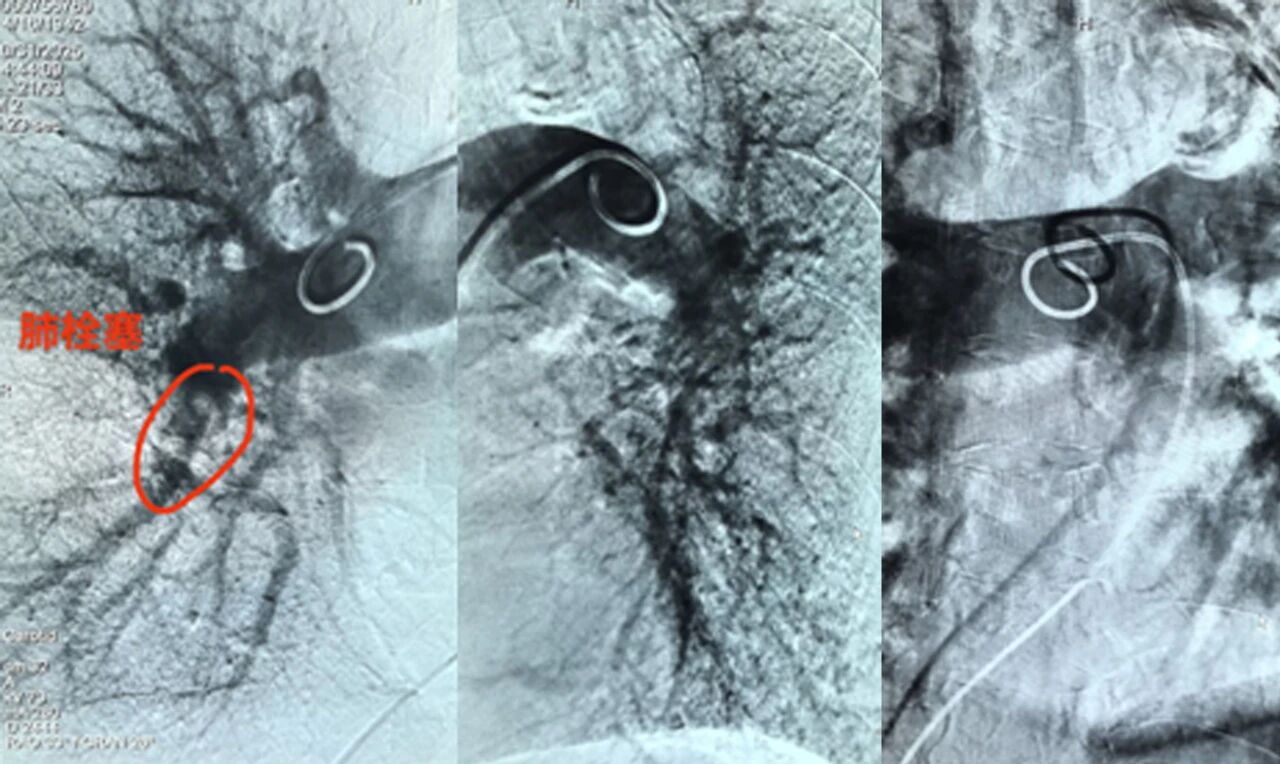

近日,沧州市第四医院(南皮县人民医院)成功开展首例肺动脉造影+溶栓术,此项技术填补了医院肺血管介入领域的空白,标志着我院急性肺栓塞救治水平达到全省同级医院先进行列,为高危肺栓塞、慢性血栓栓塞性肺动脉高压患者提供了精准治疗新选择,进一步提升区域内急危重症救治效率。

面对这一紧急情况,心血管内二科邢文华主任带领介入团队密切协作,迅速制定个性化手术方案,术中精准操作导管,在30分钟内完成血栓定位与溶栓药物输注。术后密切监测患者生命体征,提供24小时精细化护理,确保患者平稳恢复。

肺动脉造影术作为一种精准、微创的检查手段,能够清晰显示肺动脉的形态、结构以及血流状况,为医生准确诊断肺部疾病提供了关键线索。无论是复杂的肺动脉栓塞,还是难以察觉的肺动脉狭窄、肺血管畸形等疾病,肺动脉造影术都是其诊断的金标准。

一是精准定位:在数字减影血管造影(DSA)引导下,医生将导管直达肺动脉栓塞部位,清晰显示血栓位置、大小及阻塞程度,避免了传统检查的盲区。

二是靶向溶栓:通过导管直接向血栓内注入溶栓药物,药物浓度高、作用直接,可快速溶解血栓,恢复肺血流,同时显著降低全身出血风险。